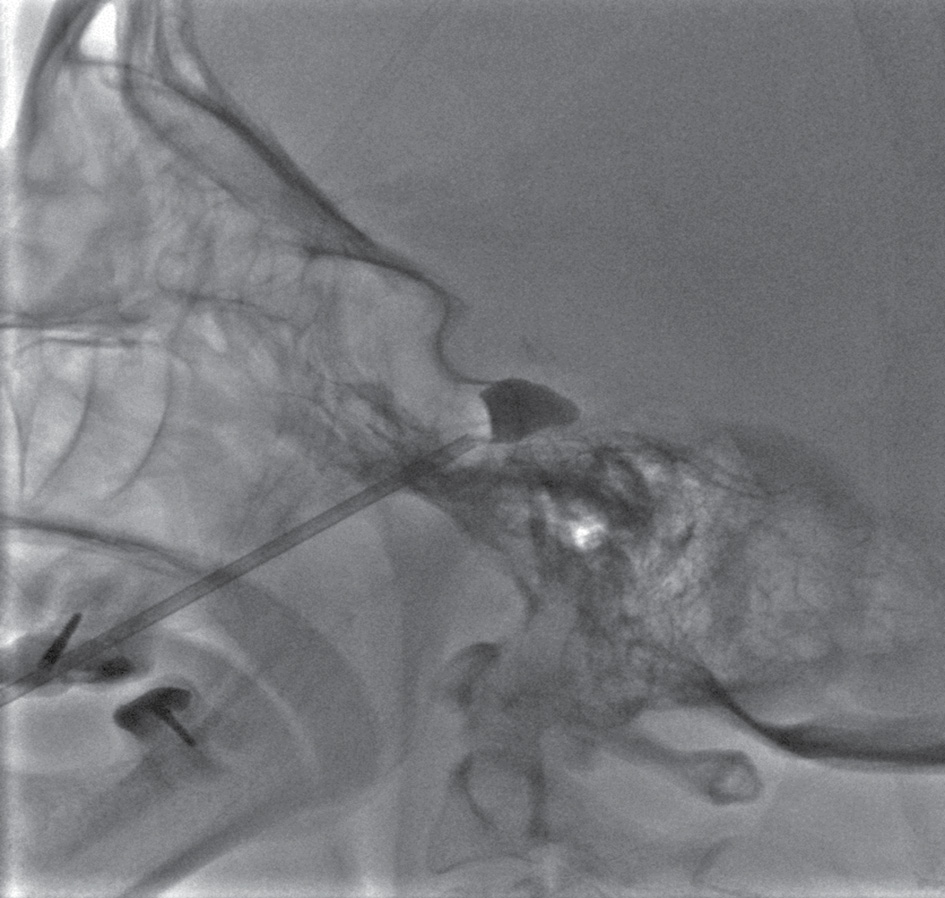

Суть хирургического лечения заключается в компрессии гассерового узла путем пункции овального отверстия через подвисочную ямку с помощью набора Муллона, баллоном-катетером, в котором временно создается давление. Выполняют переднелатеральный доступ, при котором пункционную иглу длиной 8–10 см вводят примерно на 3 см латеральнее угла рта на уровне верхнего второго моляра; иглу направляют медиально, вверх и дорсально. Кончик иглы ориентируют на зрачок (если смотреть спереди) и середину скуловой дуги (если смотреть сбоку). Игла должна пройти кнаружи от полости рта между ветвью нижней челюсти и верхней челюстью, затем латеральнее крыловидного отростка, и проникнуть в полость черепа, в среднюю черепную ямку через овальное отверстие. Контроль положения иглы осуществлялся с помощью электронно-оптического преобразователя, введение иглы проводили до уровня верхней границы спинки турецкого седла (рис. 1). Через иглу до уровня тройничного вдавления пирамиды височной кости, в меккелеву полость, проводят баллон-катетер. Баллон раздувается смесью контраста с физиологическим раствором (не более 1 мл) и приобретает при этом чаще грушевидную форму. Экспозиция компрессии длится 10 мин, после чего иглу и сдутый баллон одномоментно удаляют. Выполняют гемостаз с давлением на место пункции — на 1–2 мин, после чего накладывают асептическую наклейку.

Рис. 1. Баллонная микрокомпрессия гассерового узла

Fig. 1. Balloon microcompression of Gasserian ganglion